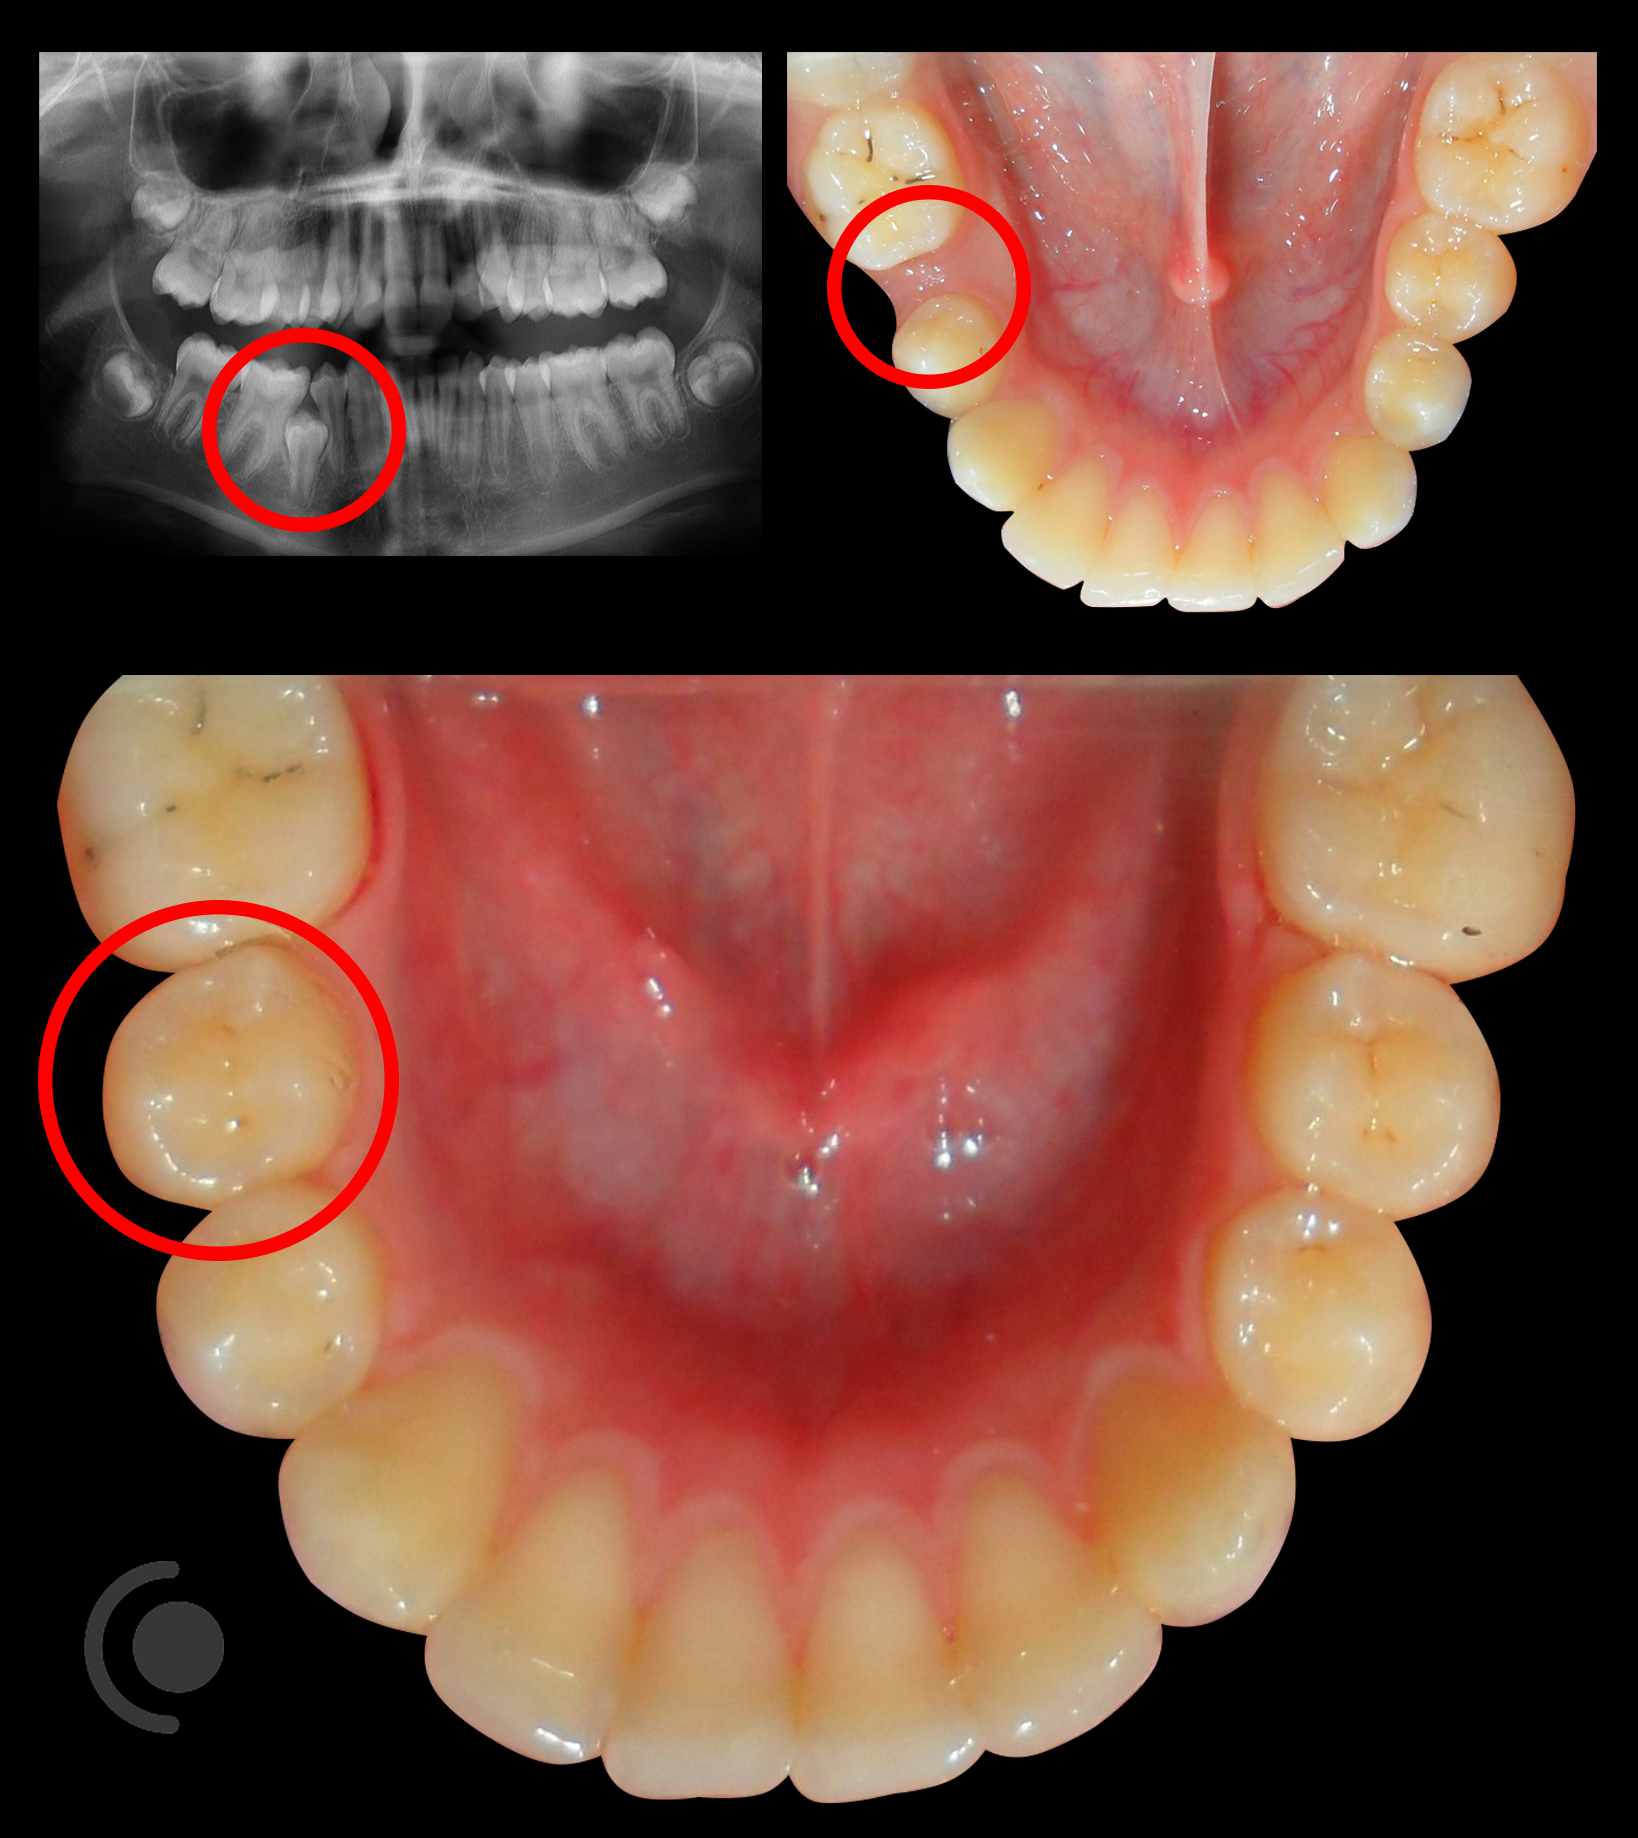

O našoj kvaliteti najbolje govore naši rezultati!

Centar za ortodonciju Petra Džapo